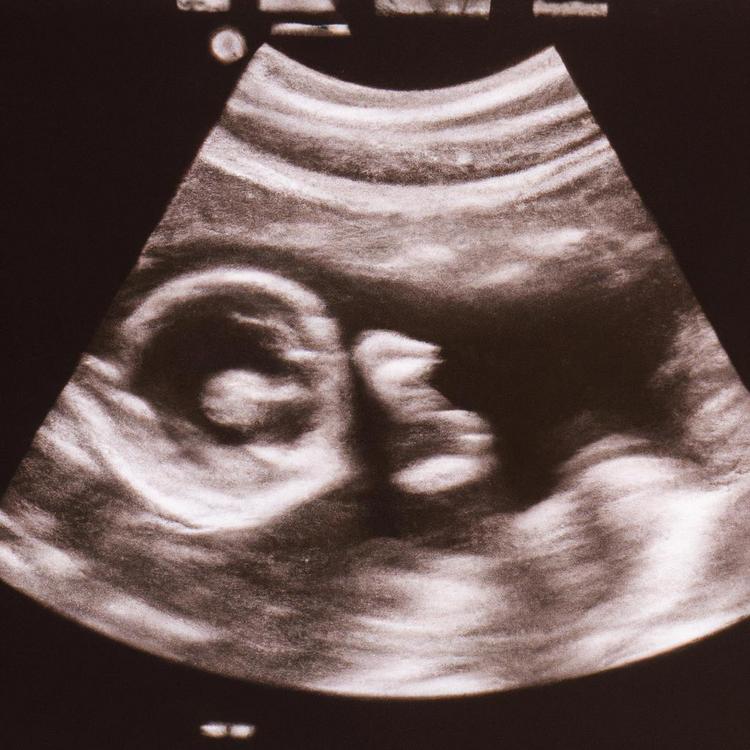

Podczas 40 tygodni ciąży dziecko przechodzi niesamowity proces rozwoju. Od maleńkiej zarodkowej komórki do pełnoprawnego noworodka – każdy tydzień oznacza kolejny etap rozwoju.